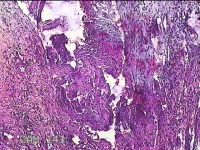

右卵巢囊肿壁

性别

女

年龄

36岁

临床诊断

右卵巢子宫内膜异位囊肿 盆腔炎性疾病后遗症

一般病史

痛经5年,加重3月。

标本名称

大体所见

灰白暗红色囊壁样组织4.5x3.3x0.8cm一堆,表面光滑,因已切开,囊内容物已流失,囊壁厚0.1cm。

图1